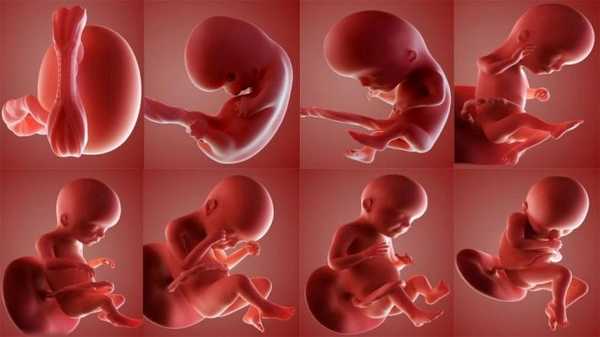

На протяжении всего периода беременности фетометрию плода проводят трижды, по одному разу на каждый триместр.

- В 1 триместре, на 11-12 неделе, определяется предполагаемая дата появления ребенка на свет. При обследовании крайне важно исключить хромосомные аномалии и существенные пороки в развитии плода. Особое внимание нужно обратить на КТР (копчико-теменной размер) и ОЖ (окружность живота). Также измеряется толщина воротникового пространства и длина носовой кости.

- Во 2 триместре, на 20-22 неделе, проверяется отсутствие нарушений во внутриутробном развитии. Измеряются бипариетальный размер головы, КТР, окружность головы (ОГ), живота, лобно-затылочный размер. При этом исследовании уже можно узнать пол ребенка.

- В 3 триместре, на 32—33 неделе, проверяется самочувствие ребенка, измеряются окружность головы и живота. Дополнительно специалист по ультразвуковой диагностике определяет симметричность развития конечностей, вес, рост плода. С помощью этих показателей выбирают способ родов — естественным путем или с помощью кесарева сечения. Второй способ предпочтительнее при крупных размерах плода, если у матери первая беременность или узкий таз.